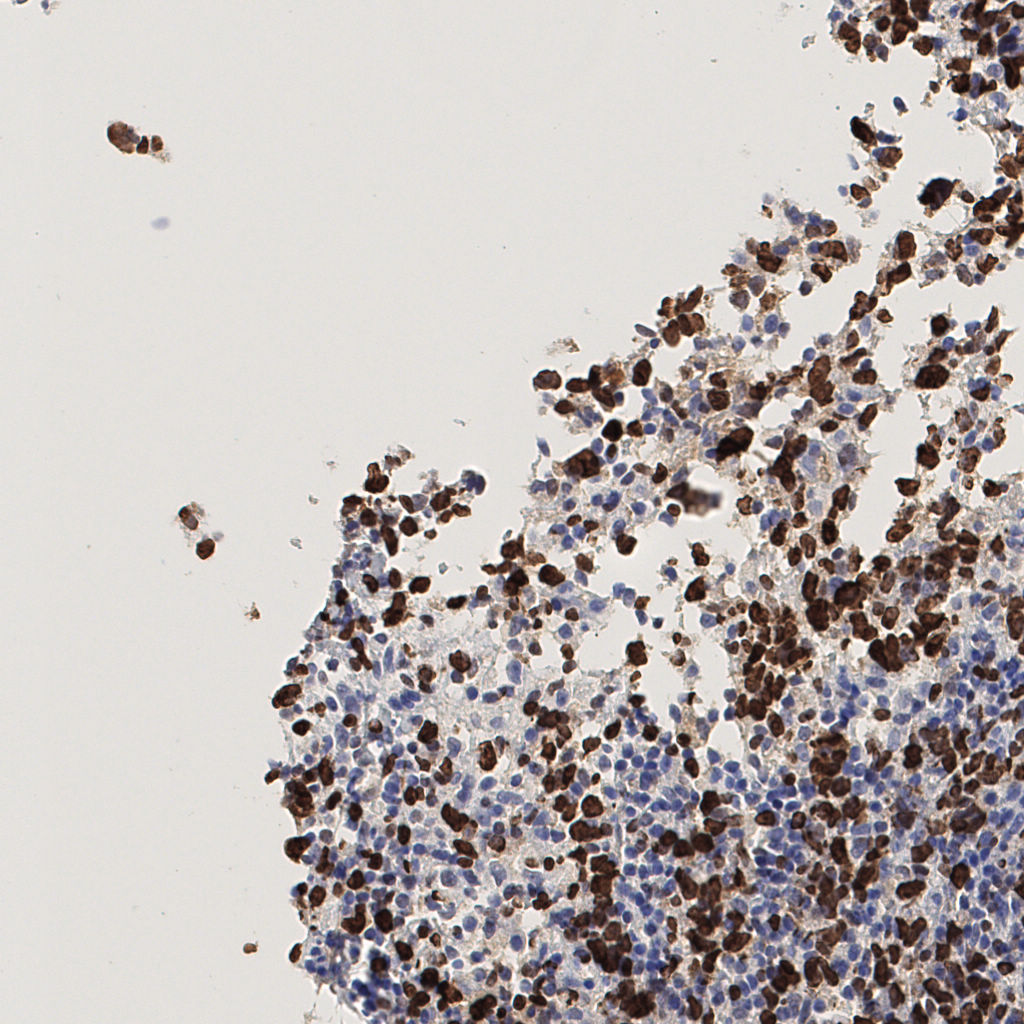

slice_42_7_x37632_y6272.png

slice_42_7_x37632...